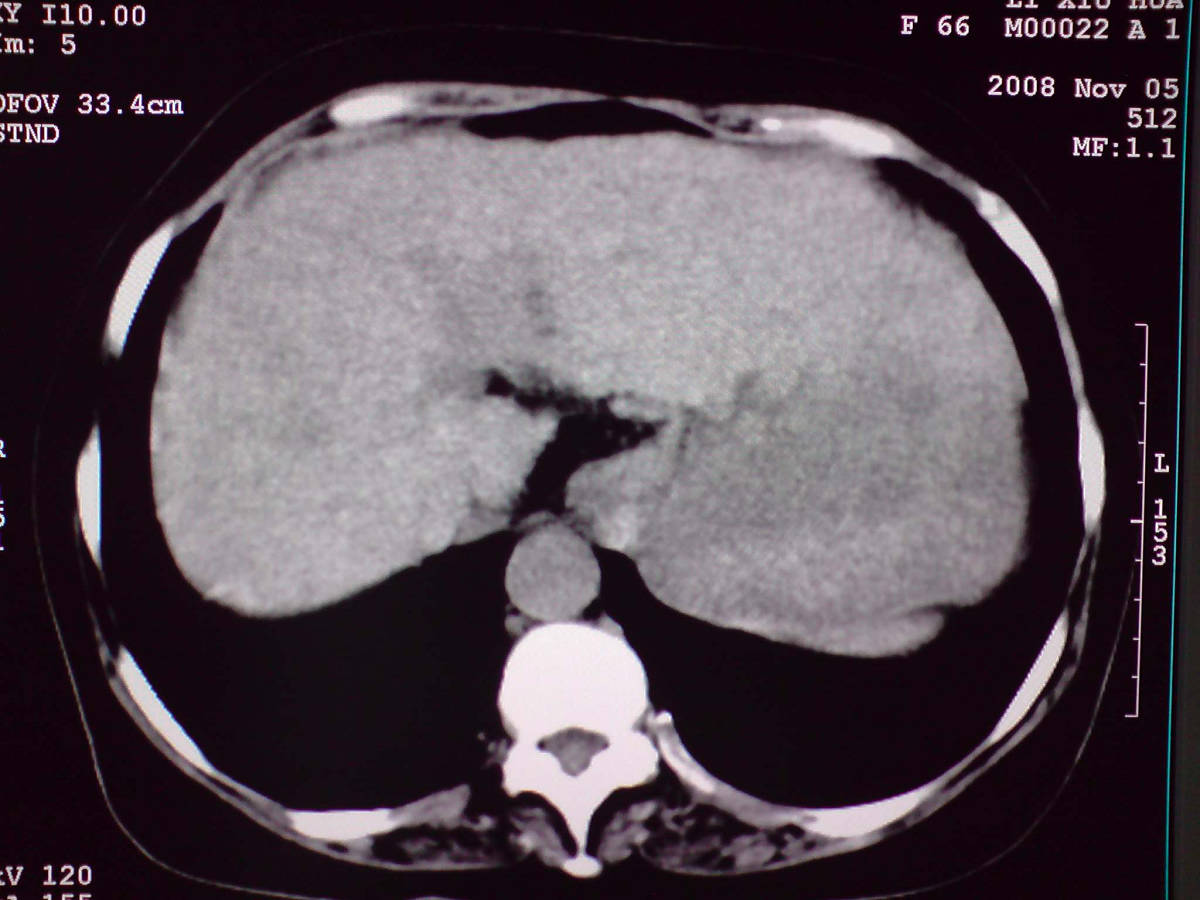

女性,60岁,上腹不适、自感胃部疼痛

小网膜区见类圆形软组织密度肿块,密度不均,内见不规则低密度区,与肝左叶分界模糊,肝脏体积缩小,密度不均匀,边缘呈波浪状,尾状叶明显增大,脾脏下缘明显超出肝脏下缘。

意见:肝硬化并外生性肝癌,建议增强扫描。

肝脏比例失调,形态失常,外缘呈波浪状,腹腔内肿块内见低密度区并与肝脏界限欠清

考虑外生性肝癌,左肺下叶占位,肝硬化

有肝硬化背景,肝胃间隙见不规则形,且密度不均匀的占位性病变,与肝左叶分界不清,首先考虑外生性肝癌可能性大,不排外肝胃间隙恶性占位肝脏受侵可能性。左肺下叶结节影,其内见空泡征,边缘见毛刺,从一元化的角度首先考虑转移。

1 肝脏各叶比例失调,形态失常,外缘呈波浪状。右叶萎缩,左叶 尾叶增大。2 腹腔内软组织密度肿块,低于肝实质密度,内见低密度区,并与肝脏界限欠清。腹膜后见肿大淋巴结,并与腹腔肿块关系密切。3 左肺下叶肿块,见边缘毛刺征及胸膜凹陷征,并与近肺门侧见异常血管相连。

综合考虑:左下肺周围性肺癌伴腹腔 腹膜后淋巴结转移!另:肝硬化!

1肝胃韧带区域一肿块,肿块上缘与肝左叶相连。肝硬化。考虑肝外生型肝癌可能性大,不除外间质瘤。2左肺下叶背段一结节,有偏心性空洞,长毛刺,其周有多发小结节。考虑结核可能性大。

感谢大家的讨论,今天拿到病理结果是肝细胞癌